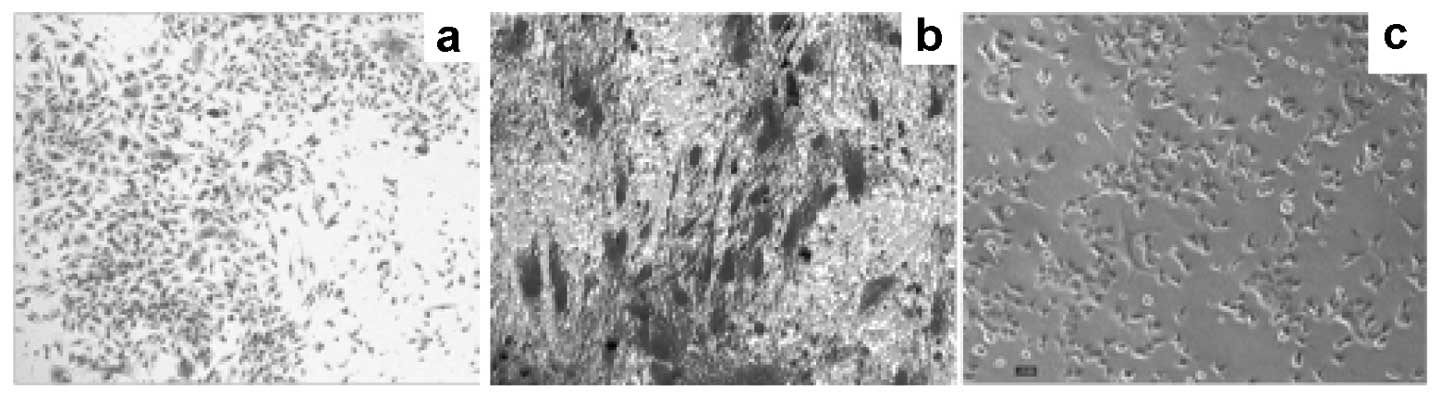

Prostate cancer (PCa) is the most common type of cancer worldwide. Mesenchymal stem cells (MSCs) can also be utilized as ‘tumor stromal cells’, which are associated with invasive and metastatic malignant tumor cells. Our study aimed to investigate MSCs in prostate tumors and normal MSCs and evaluate their differential characteristics. Normal MSCs (BMMSCs) were isolated from the femur and tibia of normal mice; prostate tumor MSCs (PCa-MSCs) were obtained from prostate tumors implanted in mice. These two types of MSCs were induced to differentiate into adipocytes, bone cells and chondrocytes. Growth curves were used to analyze the growth ability of PCa-MSCs and BMMSCs. Tritium-labeled thymidine (3H-TdR) was used to evaluate cell proliferation of RM-1 stimulated by MSCs. The time taken for PCa-MSCs to reach 90% confluence was markedly shorter than that of BMMSCs (8-10 vs. 12-14 days). The differentiation ability of PCa-MSCs was similar to that described in previous reports. The growth ability of PCa-MSCs was significantly higher than that of BMMSCs. The proliferative activity of PCa-MSCs was also higher than that of BMMSCs. Our data showed that PCa-MSCs exhibit identical characteristics when compared with those of MSCs. Additionally, their proliferative activity and growth ability were significantly higher when compared with these values in BMMSCs, which appear to have an intrinsic, cell-specific capacity to localize to PCa. The possible role of PCa-MSCs in the process of PCa development requires further clarification.

Figure 1